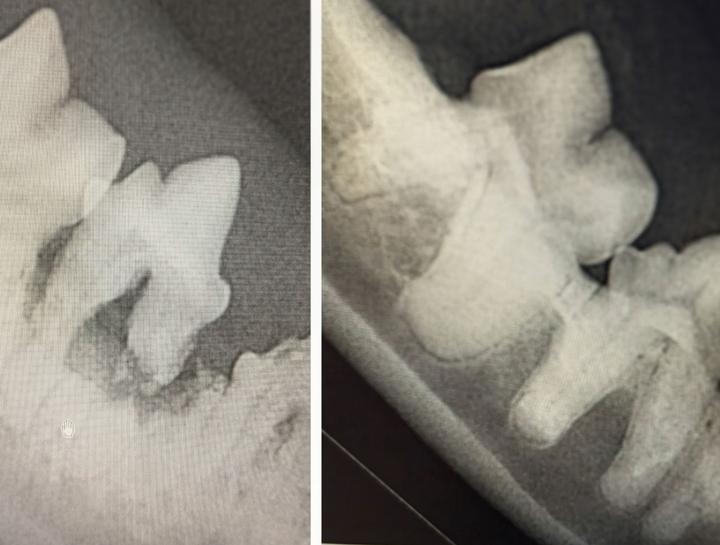

Digital Dental Radiology

Insight into underlying issues.